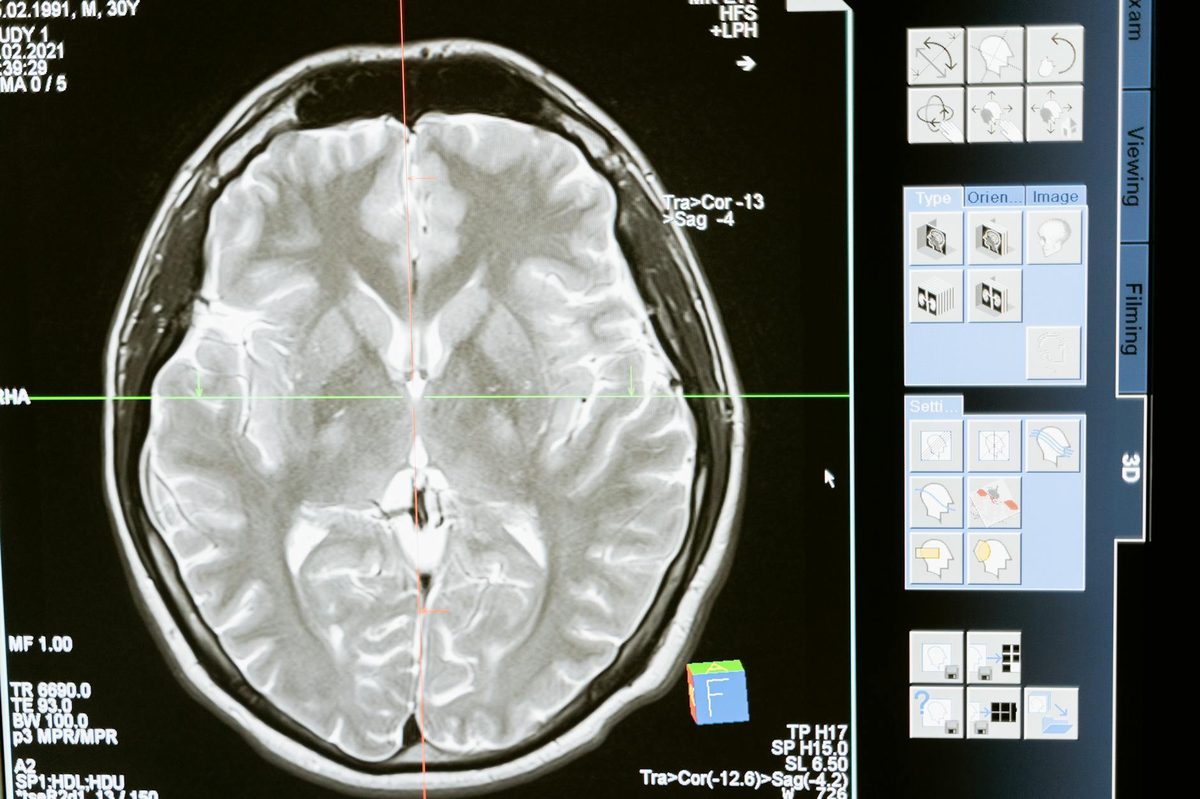

Prima's approach—training on 200,000 real MRI studies with physician diagnoses—directly addresses Watson's central failure. The system learns from actual clinical practice rather than synthetic cases or literature abstracts.